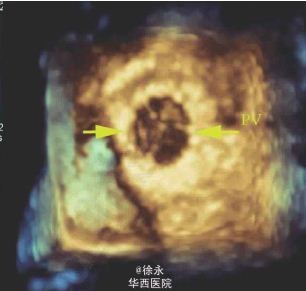

患者,女性,39 岁,25 年前因“法洛四联症”行外科治疗,近月出现活动后胸闷、心慌。超声心动图示外科术后补片下缘室水平残余分流,肺动脉瓣返流(重度)。住院期间先后行室缺残余漏封堵术+经皮导管肺动脉瓣置入术。